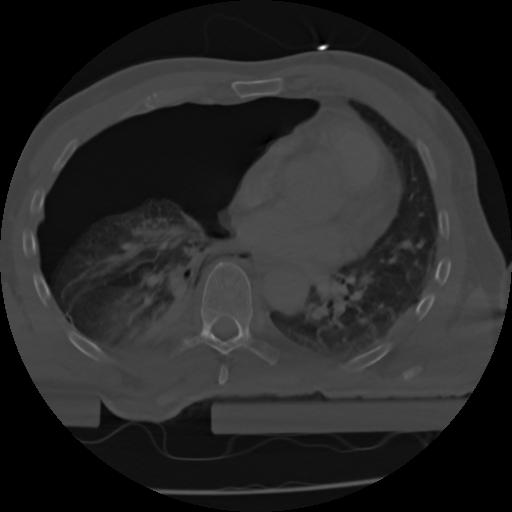

21 ANGIO,CE,Axial,3.0,ANGIO,,